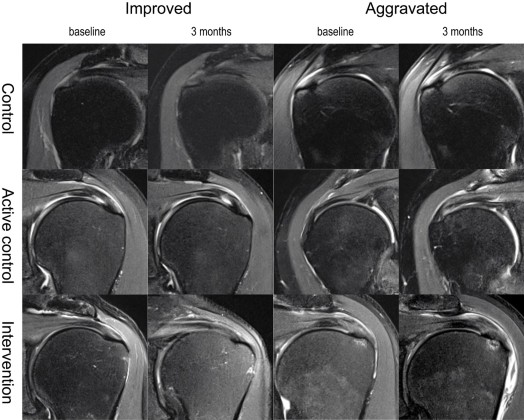

The severity of pain was assessed by visual analog scale (pain VAS) during activity and resting. Shoulder function was assessed by determination of the American Shoulder and Elbow Surgeons (ASES) score, a questionnaire composed of both physician- and patient-rated components. Patients graded the difficulty performing specific daily activities using a 4-point Likert scale. This method has been shown to be reliable and to yield valid results for rotator cuff disorders11. The size of the tear was evaluated by MRI; follow-up images were qualitatively compared with baseline images using a 5-point Likert scale, as follows: markedly increased, slightly increased, stationary, slightly decreased, and markedly decreased. This was used for the statistical analysis, however, for the figure, the 5-point scale was compressed to either “improved”, “no change”, or “aggravated” for visual clarity. Follow-up images were graded by two radiologists (H.S.H, Y.H.J). The assessors were blinded to the intervention and the follow-up period. The inter-rater reliability was good (interclass correlation [standard deviation] = 0.638 [0.348–0.799])12.

The mean (standard deviation) changes in pain VAS during activity at 3 months after intervention were − 1.37 (2.85), − 1.48 (2.37), and − 3.0 (2.56) in the intervention, active control, and control groups, respectively. There were no significant differences between groups (p = 0.35), although the saline group showed the most improvement (i.e., largest negative net VAS, indicating decreased pain). Pain VAS during activity or at rest, ASES scores, and rates of change in these variables did not differ according to group. However, all clinical variables improved over time (Figs. 2), and MRI grading of tear size showed no significant differences (Fig. 3, Supplementary figure).

Although the primary outcome measure is not a pitfall of the study, it may be insufficient to assess the effect of the MSCs. Considering the regenerative characteristics of MSC, the intervention might have caused structural changes that did not lead to clinical improvement. We thoroughly reviewed the MRI images both separately and collaboratively to find any meaningful structural change. We also applied the semi-quantitative method adopted in the study by Jo et al.8 and reviewed the ultrasonographic examinations that were not depicted in the original protocol. However, we could not observe any difference in regard of structural change between groups.